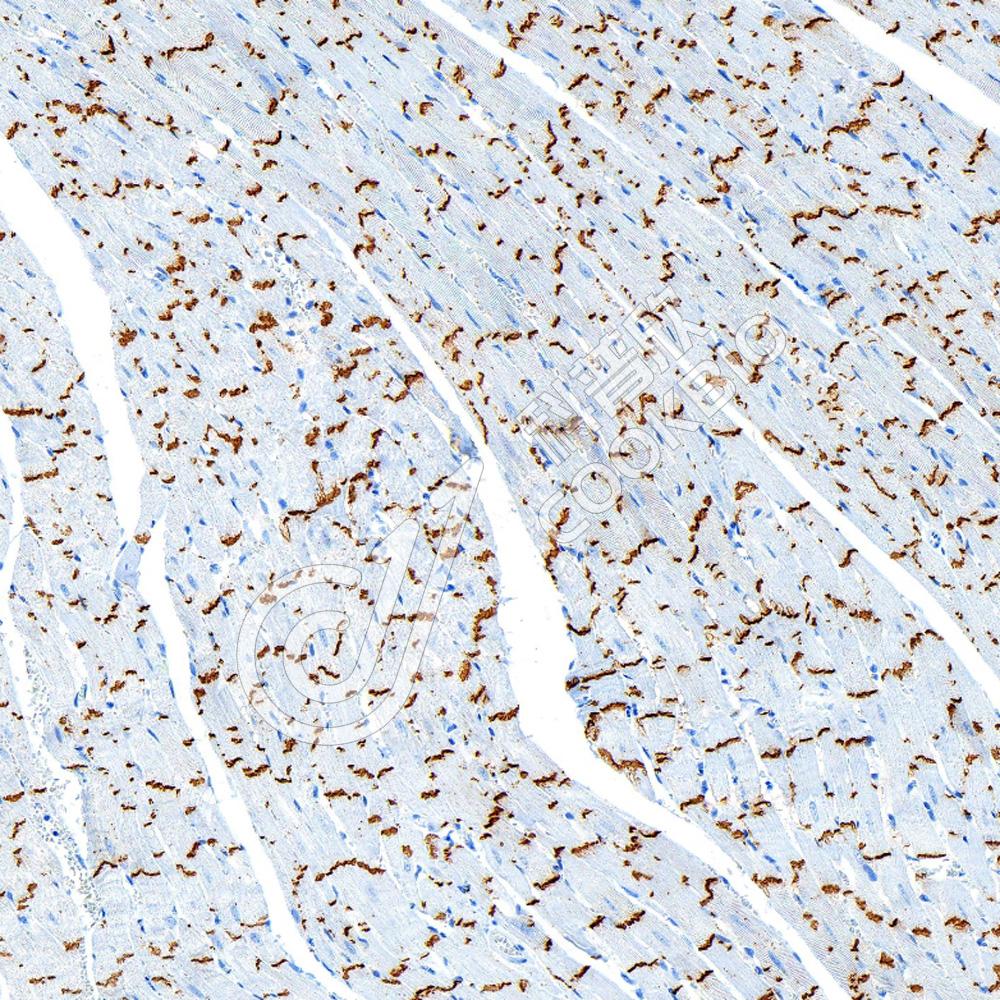

IHC检测Connexin 43/GJA1蛋白(货号 K545702).

样品: 小鼠心, 4%多聚甲醛 (货号KSG1101) 固定12-24小时.

抗原修复: 柠檬酸抗原修复液(干粉, pH 6.0) (KSG1201), 高压锅均匀喷气计时2分钟.

—抗: 1: 1500稀释, 4℃ 孵育过夜.

二抗: S-vision免疫组化多聚二抗(山羊抗兔),即用型 (货号KB3906), 室温孵育20分钟.

样品: 大鼠心, 4%多聚甲醛 (货号KSG1101) 固定12-24小时.